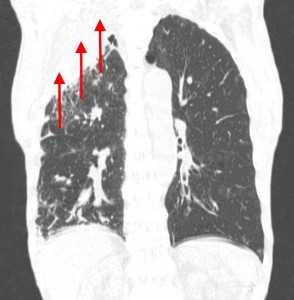

Лимфогенные метастазы легких на КТ выглядят как множественные мелкие диссеминированные очаги. Они расположены вдоль междольковых перегородок и плевры. Картина напоминает туберкулез и саркоидоз, и в этой связи часто требует уточнения. Вместе с лимфогенными метастазами легких почти всегда обнаруживаются патологические изменения (увеличение) лимфатических узлов средостения.

Лимфогенные метастазы на рентгене и КТ выглядят как множественные мелкие очаги с диссеминированным распространением, локализованные в междольковых перегородках, в плевральных листках. Вокруг можно видеть характерную картину ракового лимфангиита. Кроме того, практически всегда выявляются патологически измененные и увеличенные лимфатические узлы средостения. Лимфогенное метастазирование необходимо дифференцировать с милиарным туберкулезом, саркоидозом. Иногда это требует привлечения Второго мнения.

Лимфогенные метастазы проявляются увеличением лимфатических узлов средостения в сочетании с мелкоочаговой диссеминацией с очагами до 2-3 мм в диаметре вблизи плевры и в междольковых перегородках, а также по ходу бронхов и сосудистых пучков.